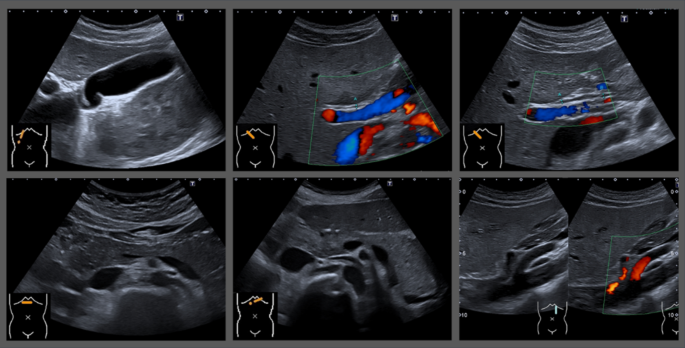

4. 복부 초음파는 장내 가스·음식 잔여물이 결과를 왜곡

초음파 영상이 음식물·가스로 가려지는 모습

복부 초음파는 소화기관 주변을 관찰하는 검사입니다.

음식이나 공기가 있으면 초음파가 통과하기 어려워 간·담낭·췌장·위 주변 장기의 영상이 선명하게 보이지 않습니다.

특히 담낭(쓸개)은 식사 후 수축하기 때문에 비워진 상태에서는 제대로 관찰이 어렵습니다.